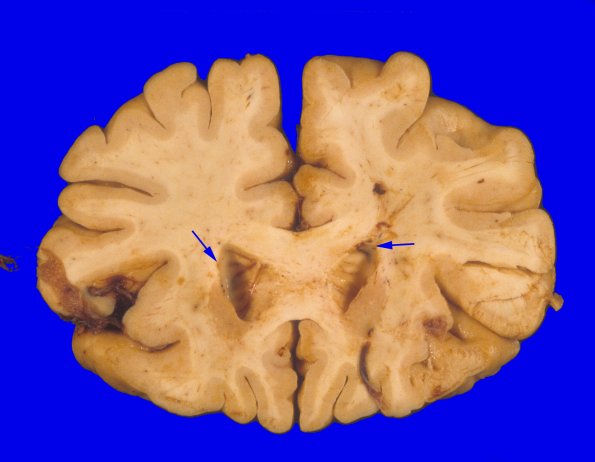

2A1 At autopsy the unfixed brain weighed 1350g. The leptomeninges are thin, tan brown and unremarkable, without areas of thickening or exudate. Coronal sections through the cerebral hemispheres demonstrate widening of the sulci, and dilatation of the lateral ventricles, consistent with atrophy. The ependymal lining (arrows) is granular throughout. There are no basal ganglia “soap bubble” lesions often seen with cryptococcus